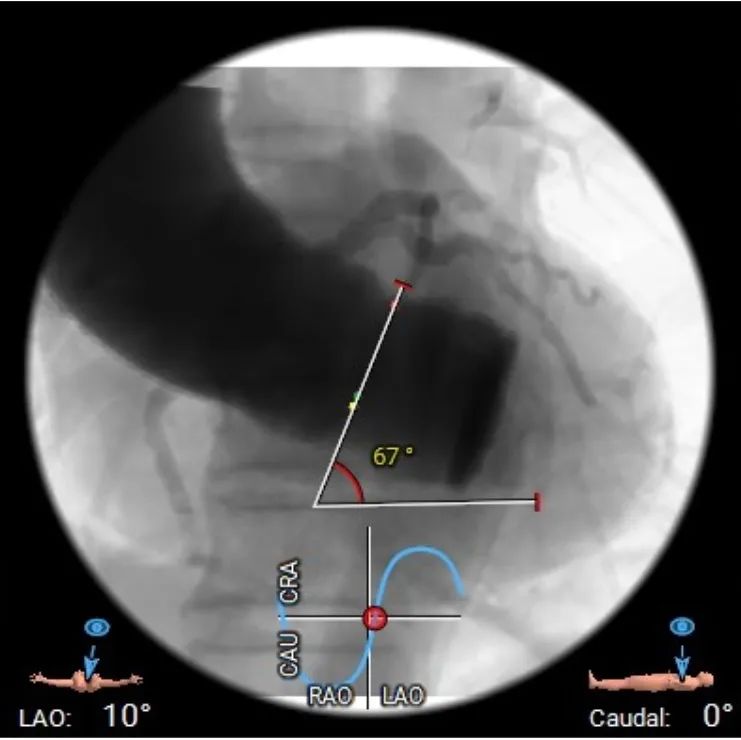

心脏水平夹角67°,横位心;

患者心脏水平夹角偏大,升主动脉存在扩张,器械进入存在一定血管损伤风险,瓣膜释放同轴性可能欠佳;